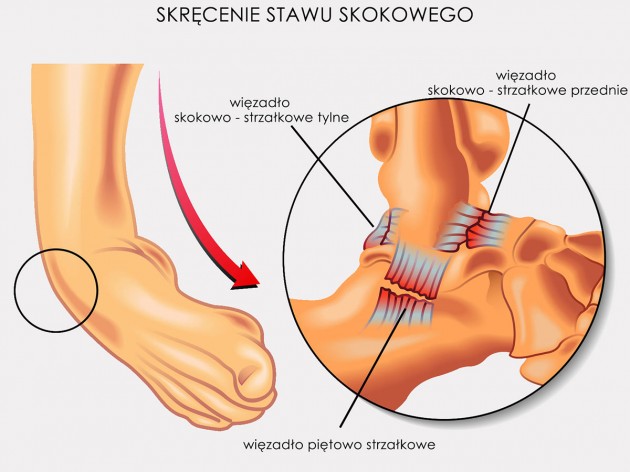

Skręcenie kostki

W Stanach Zjednoczonych skręcenie kostki jest 1 na 10 powodów wizyty na ostrym dyżurze. Obejmuje ono boczną część kostki, czyli więzadło strzałkowo-skokowe przednie (AFTL) i strzałkowo-piętowe (CFL). Wyróżniamy trzy stopnie urazu: łagodny (częściowe uszkodzenie samego AFTL), umiarkowany (całkowite uszkodzenie AFTL i częściowe CFL) i ostry (całkowite uszkodzenie AFTL oraz CFL). Do skręcenia kostki najczęściej dochodzi na skutek nagłej zmiany kierunku ruchu (stopa w inwersji), szczególnie na nierównym podłożu (np. trawie) oraz gdy zawodnik po skoku ląduje na stopie innego zawodnika, dlatego najczęściej obserwujemy je w koszykówce, siatkówce i piłce nożnej.

W Stanach Zjednoczonych skręcenie kostki jest 1 na 10 powodów wizyty na ostrym dyżurze. Obejmuje ono boczną część kostki, czyli więzadło strzałkowo-skokowe przednie (AFTL) i strzałkowo-piętowe (CFL). Wyróżniamy trzy stopnie urazu: łagodny (częściowe uszkodzenie samego AFTL), umiarkowany (całkowite uszkodzenie AFTL i częściowe CFL) i ostry (całkowite uszkodzenie AFTL oraz CFL). Do skręcenia kostki najczęściej dochodzi na skutek nagłej zmiany kierunku ruchu (stopa w inwersji), szczególnie na nierównym podłożu (np. trawie) oraz gdy zawodnik po skoku ląduje na stopie innego zawodnika, dlatego najczęściej obserwujemy je w koszykówce, siatkówce i piłce nożnej.

Należy pamiętać, że uraz dotyczy każdego rodzaju sportu i aktywności fizycznej, dlatego niezmiernie istotna jest profilaktyka w postaci profesjonalnego zaopatrzenia jakim jest orteza stawu skokowego AM-OSS-13.

Należy pamiętać, że uraz dotyczy każdego rodzaju sportu i aktywności fizycznej, dlatego niezmiernie istotna jest profilaktyka w postaci profesjonalnego zaopatrzenia jakim jest orteza stawu skokowego AM-OSS-13.